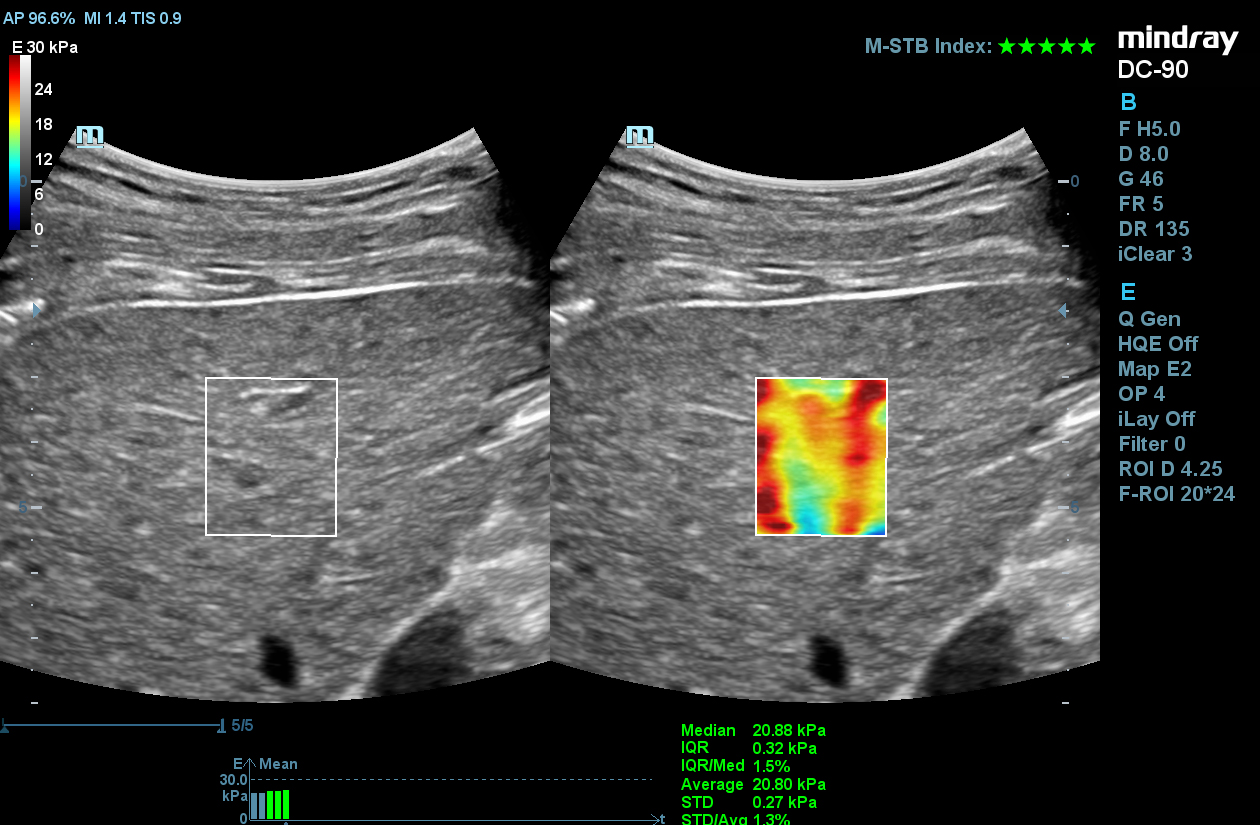

STE

Mindray’s Sound Touch Elastography (STE) utilizes exclusive Ultra-Wide Beam Tracking technology to provide comprehensive quantification metrics and dynamic visual display of tissue stiffness for enhanced diagnostic confidence. Using real-time and rapid data acquisition from a wide beam single pulse, STE is designed to reduce noise caused by motion artifact for improved efficiency and accuracy of measurements.